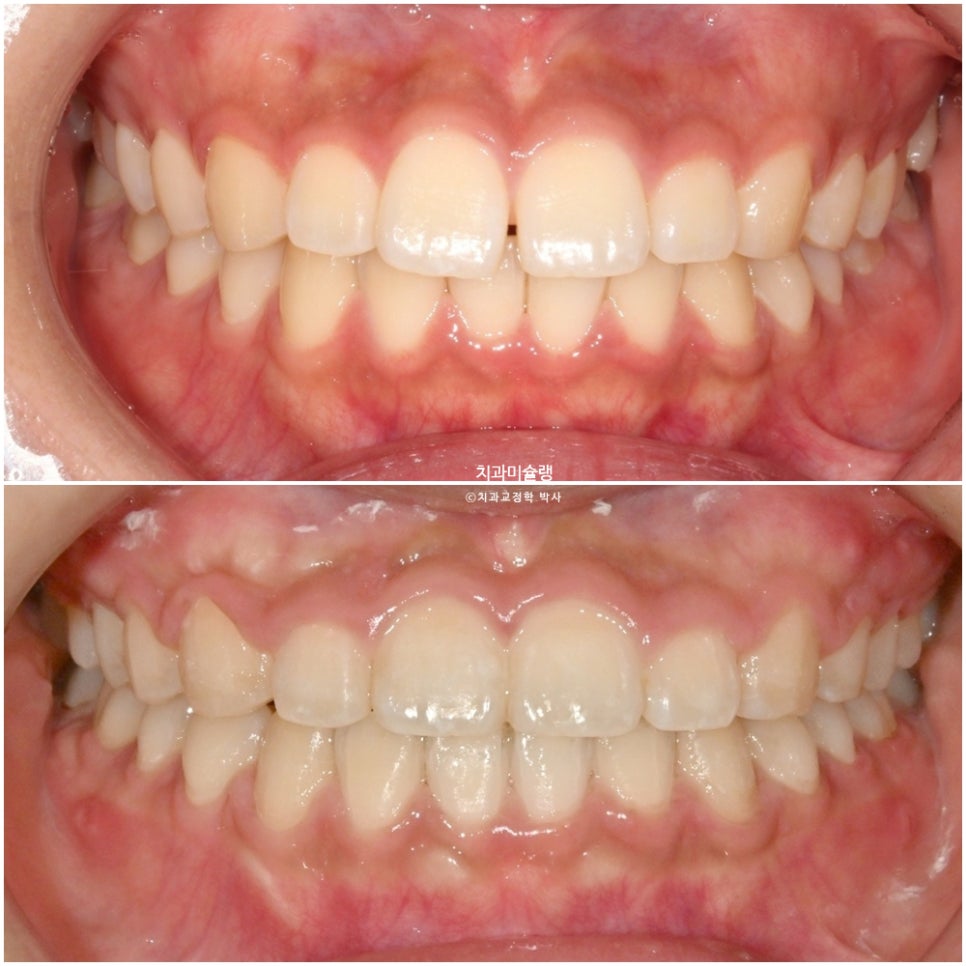

치료 전후 비교

이제 전후비교 볼게요.

교정 전후 사진을 비교해보면 위 앞니 수직 길이가 짧아진게 보입니다.

앞니가 위로 함입되며 치아가 잇몸속으로 쏙 들어간 셈인데, 치아를 과도하게 덮는 잇몸은 잇몸성형으로 치아 개개의 가로 세로 비율을 회복하기 위해 간단하게 걷어내는게 심미적으로 좋습니다.

앞니 돌출이 해소되어 입 다무는게 한결 편해졌으므로, 더이상 입술 사이로 앞니가 빼꼼 보이지 않습니다.

환자분은 잇몸성형을 여전히 고민중이지만, 잇몸성형 후 미소가 어떻게 달라지는지도 나중에 기회되면 포스팅 할게요.